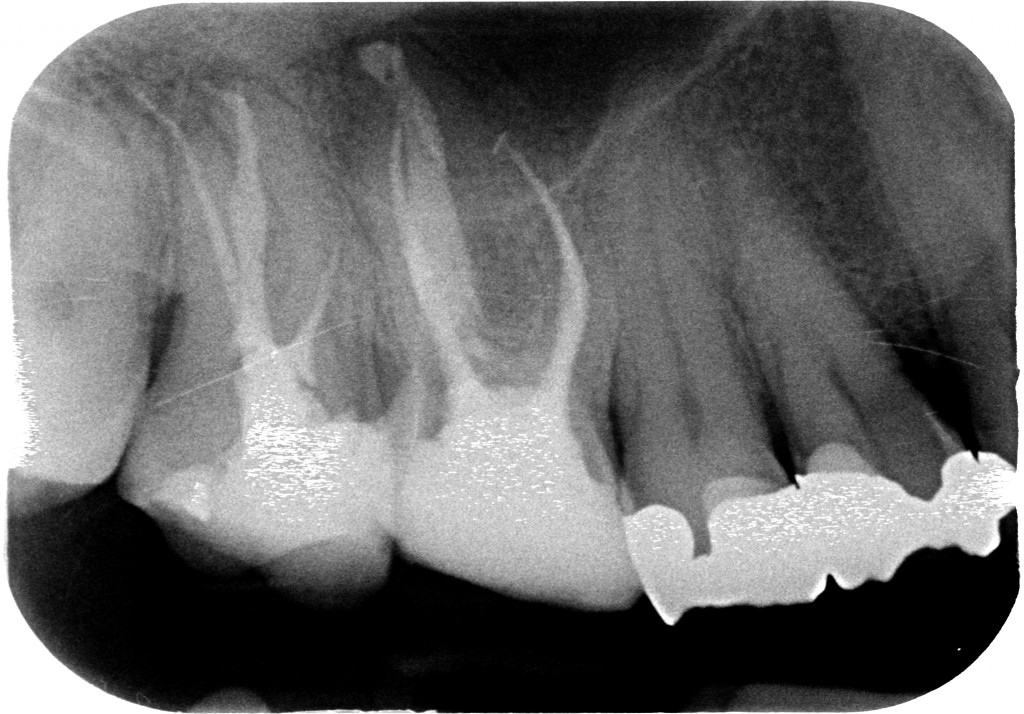

Questo sabato non ha fatto eccezione e mi sono trovato in agenda un ritrattamento di un 1.7 che già dalla radiografia preoperatoria mi ha fatto drizzare le antenne.?

Vedi quel canale mesio-vestibolare? Per esperienza so che quando il dentista che ci ha preceduto è in grado di arrivare in apice su due canali e sul terzo si perde prima della curva di una radice possono essere capitate solo due cose, perchè escludo che sia semplicemente un incapace che non sa fare l’endodonzia:

Ed ecco la rx.